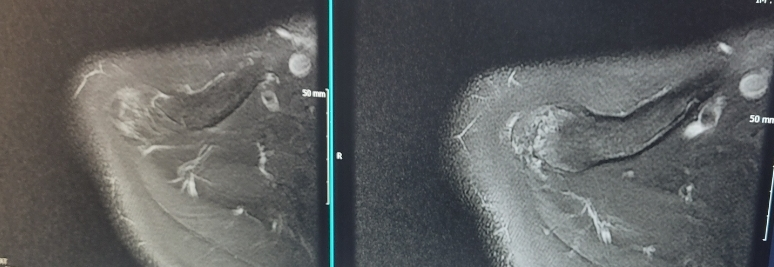

초음파상 힘줄 손상이 있어, 우측 어깨 정확하게 확인하기위해 MRI 촬영을 했고, MRI상 견갑하건 부분파열이 있습니다. 그리고 극상근에 기스가 나있는 상태입니다. (사진참조)

[MRI]